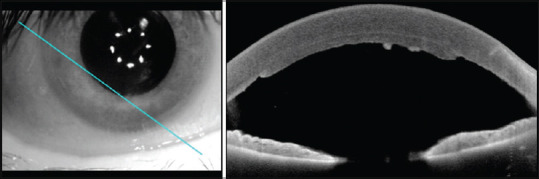

Purpose: To highlight the rarity of the endothelial rejection line, also known as the Khodadoust line, as a manifestation following Descemet's stripping automated endothelial keratoplasty (DSAEK). The objective is to present a meticulously detailed case, including imaging and anterior optical coherence tomography (OCT), to enhance understanding and recognition of this phenomenon.

Methods: A detailed case presentation involving a 50-year-old male, 3 years post-DSAEK transplantation for endothelial damage resulting from intraocular surgeries. The patient urgently sought consultation due to vision loss while under daily fluorometholone use. Clinical examination revealed acute graft rejection characterized by corneal edema, anterior chamber reaction, and the presence of keratic precipitates forming a Khodadoust line. The management approach included the initiation of a tapered dexamethasone regimen.

Results: The identified acute graft rejection, marked by the presence of a Khodadoust line, demonstrated favorable responsiveness to the initiated tapered dexamethasone regimen. Corneal OCT and imaging played crucial roles in providing detailed insights into the manifestation.